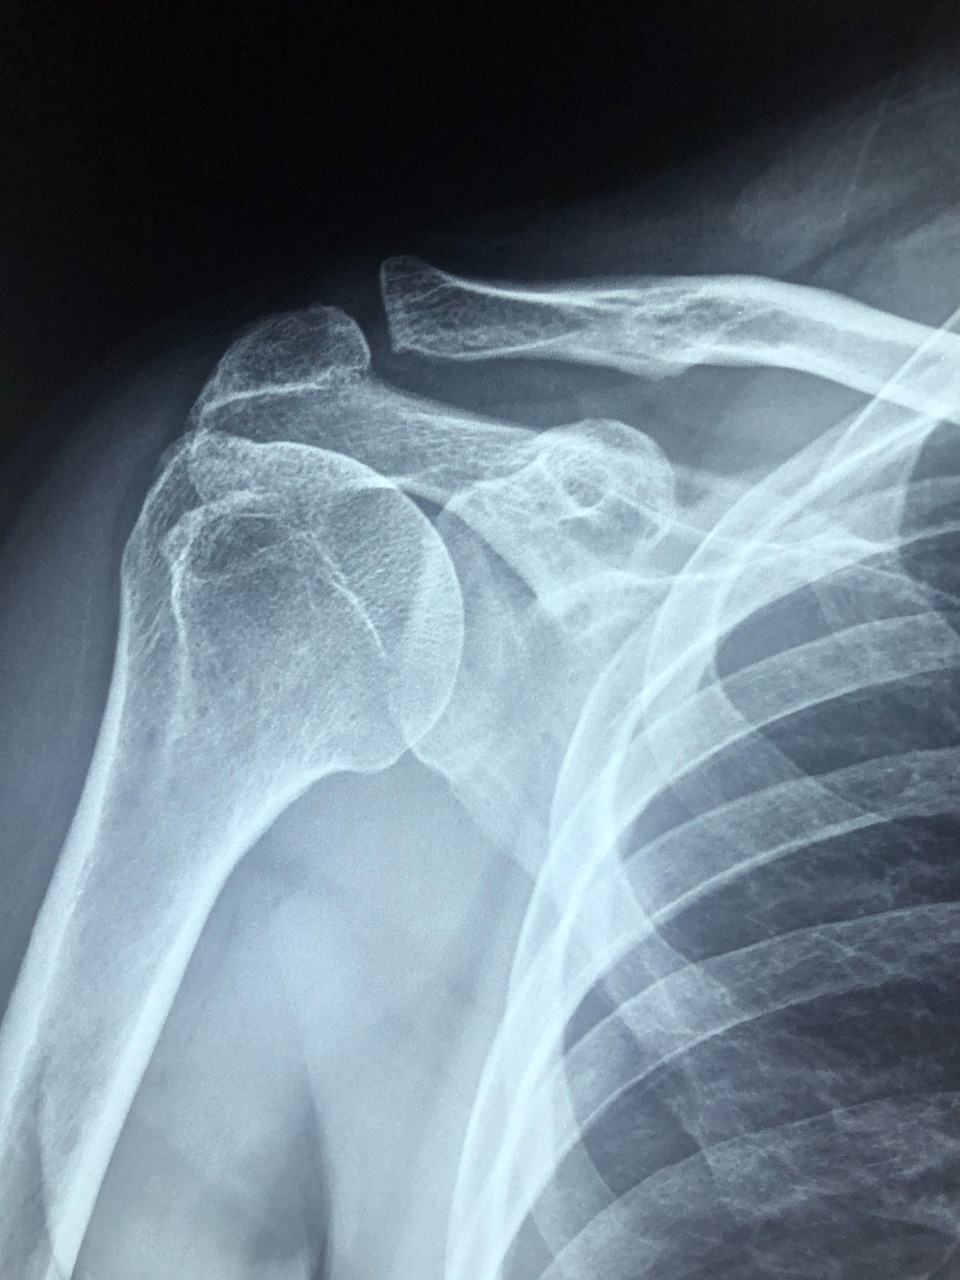

Shoulder Arthritis: Two Truths

Truth #1: Shoulder Arthritis Often Affects Both Arms For a given patient, shoulder arthritis in the ball and socket portion of the joint usually occurs in both arms. We don’t totally understand why this is. There is likely some genetic predisposition that we have yet to fully figure out. But it’s true: if you’ve got…

Arthritis in the Ball and Socket Joint Arthritis is actually relatively uncommon in this joint. But when it occurs it tends to show a distinct pattern. The hallmark of arthritis at the ball and socket shoulder joint is joint space narrowing bone spurs at the bottom of the ball portion of the joint. The patient…